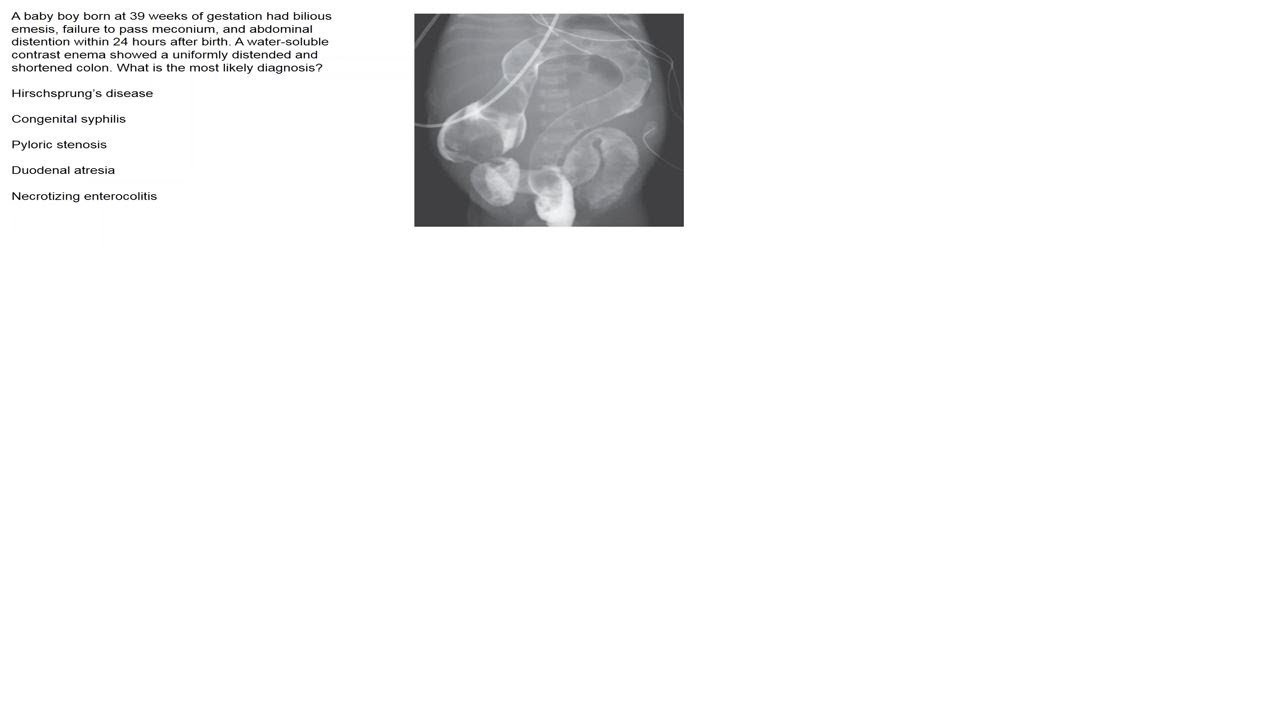

The N Engl J Med image of the week concerns a baby boy born at 39 weeks of gestation who had bilious emesis, failure to pass meconium, and abdominal distention within 24 hours after birth. A water-soluble contrast enema showed a uniformly distended and shortened colon. What is the most likely diagnosis? You are offered Hirschsprung’s disease, Congenital syphilis, Pyloric stenosis, Duodenal atresia, Necrotizing enterocolitis. We review the possibilities. Infections after placement of cardiac implantable electronic devices (CIEDs) are associated with substantial morbidity and mortality. There is limited evidence on prophylactic strategies, other than the use of preoperative antibiotics, to prevent such infections. Investigators conducted a randomized, controlled clinical trial to assess the safety and efficacy of an absorbable, antibiotic-eluting envelope in reducing the incidence of infection associated with CIED implantations. Patients who were undergoing a CIED pocket revision, generator replacement, or system upgrade or an initial implantation of a cardiac resynchronization therapy defibrillator were randomly assigned, in a 1:1 ratio, to receive the envelope or not. Standard-of-care strategies to prevent infection were used in all patients. The primary end point was infection resulting in system extraction or revision, long-term antibiotic therapy with infection recurrence, or death, within 12 months after the CIED implantation procedure. The secondary end point for safety was procedure-related or system-related complications within 12 months. The WRAP-IT study suggests that the envelope provides some protection against infection. Cryptogenic strokes (where we have no idea where the stroke came from or why) constitute 20 to 30% of ischemic strokes, and most cryptogenic strokes are considered to be embolic and of undetermined source. An earlier randomized trial showed that rivaroxaban was no more effective than aspirin in preventing recurrent stroke after a presumed embolic stroke from an undetermined source. Whether dabigatran would be effective in preventing recurrent strokes after this type of stroke is unclear. Investigators conducted a multicenter, randomized, double-blind trial of dabigatran at a dose of 150 mg or 110 mg twice daily as compared with aspirin at a dose of 100 mg once daily in patients who had had an embolic stroke of undetermined source. The primary outcome was recurrent stroke. The primary safety outcome was major bleeding. Dabigatran was no better than aspirin according to this study. In the context of kidney transplantation, genomic incompatibilities between donor and recipient may lead to allosensitization against new antigens. Investigators hypothesized that recessive inheritance of gene-disrupting variants (missing a piece, ie a small deletion) may represent a risk factor for allograft rejection. They performed a two-stage genetic association study of kidney allograft rejection. In the first stage, they conducted a recessive association screen of 50 common gene-intersecting deletion polymorphisms in a cohort of kidney transplant recipients...